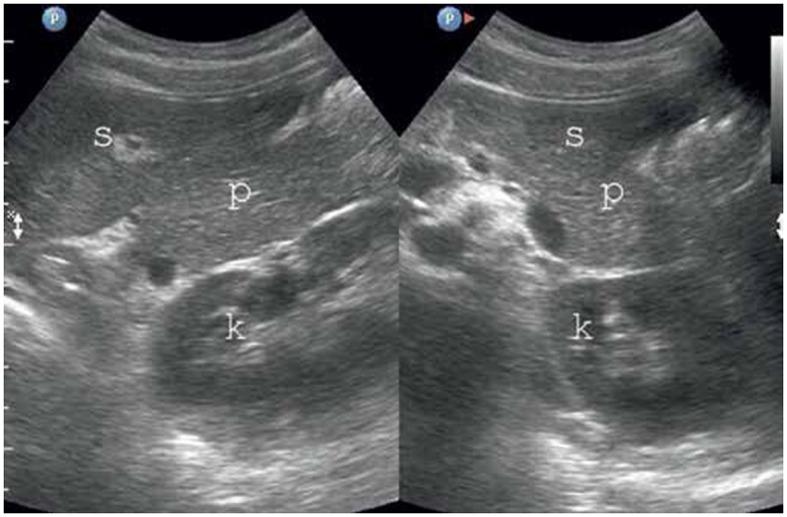

Fatty infiltration of the pancreas (FIP) has been recognized for nearly a century, yet many aspects of this condition remain unclear. Regular literature reviews on the diagnosis, consequences, and management of FIP are crucial. This review article highlights the various disorders for which FIP has been established as a risk factor, including type 2 diabetes mellitus (T2DM), pancreatitis, pancreatic fistula (PF), metabolic syndrome (MS), polycystic ovary syndrome (PCOS), and pancreatic duct adenocarcinoma (PDAC), as well as the new investigation tools. Given the interdisciplinary nature of FIP research, a broad range of healthcare specialists are involved. This review article covers key aspects of FIP, including nomenclature and definition of pancreatic fat infiltration, history and epidemiology, etiology and pathophysiology, clinical presentation and diagnosis, clinical consequences, and treatment. This review is presented in a detailed narrative format for accessibility to clinicians and medical students.

胰腺脂肪浸润(FIP)已被认识近一个世纪,但这种病症的许多方面仍不清楚。定期对FIP的诊断、后果及管理进行文献综述至关重要。这篇综述文章强调了已确定FIP为风险因素的各种疾病,包括2型糖尿病(T2DM)、胰腺炎、胰瘘(PF)、代谢综合征(MS)、多囊卵巢综合征(PCOS)和胰腺导管腺癌(PDAC),以及新的研究工具。鉴于FIP研究的跨学科性质,涉及广泛的医疗保健专家。这篇综述文章涵盖了FIP的关键方面,包括胰腺脂肪浸润的命名和定义、历史和流行病学、病因和病理生理学、临床表现和诊断、临床后果及治疗。本综述以详细的叙述形式呈现,以便临床医生和医学生查阅。